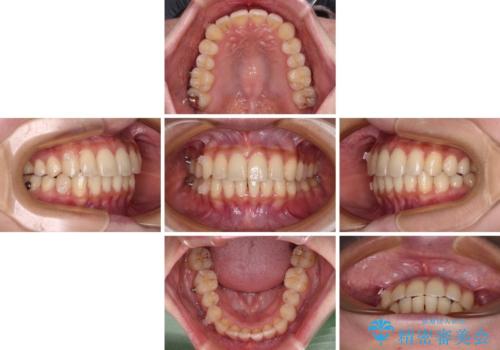

- 前歯のデコボコと強い咬みしめを気にして来院された患者様です。

インビザラインを用いて、前歯の叢生を解消するとともに、ディープバイトを改善していくこととしました。

海外へ転居する予定があったため、1日22時間以上の装着時間をしっかりと守っていただき、予定期間よりも早く、思っていた以上にきれいに仕上げることができました。